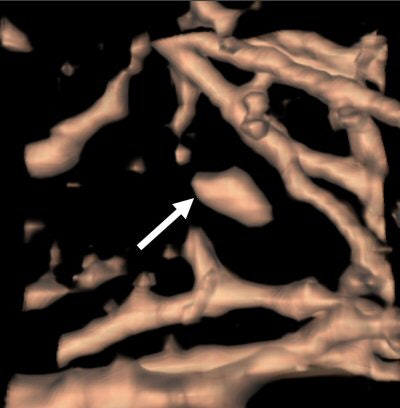

| An elongated nodule missed by all three radiologists during free search. On the axial image (above), the small nodule looks more likely to be a vascular structure with an elongated shape and parallel orientation with adjacent branching vessels. On the coronal image (below), the lesion seems more globular in the craniocaudal direction. 3D volume-rendered image (bottom) presents a discrete nodule between vessels. Although this true-positive nodule was detected by CAD, all three radiologists rejected this nodule with low confidence scores. All images courtesy of Dr. Chin Yi. |